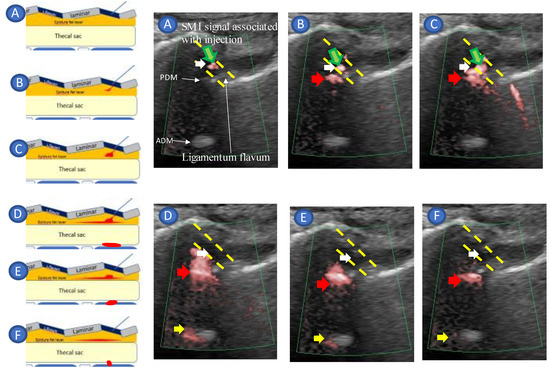

- Accurate needle tip guidance into the ligamentum flavum behind the epidural fat layer;

- Palpation of resistance by finger sense during ligamentum flavum insertion while confirming with sonography;

- Confirmation of the position of the needle tip in the ligamentum flavum;

- Tracing the spread of the drug in the epidural space using SMI during the injection.